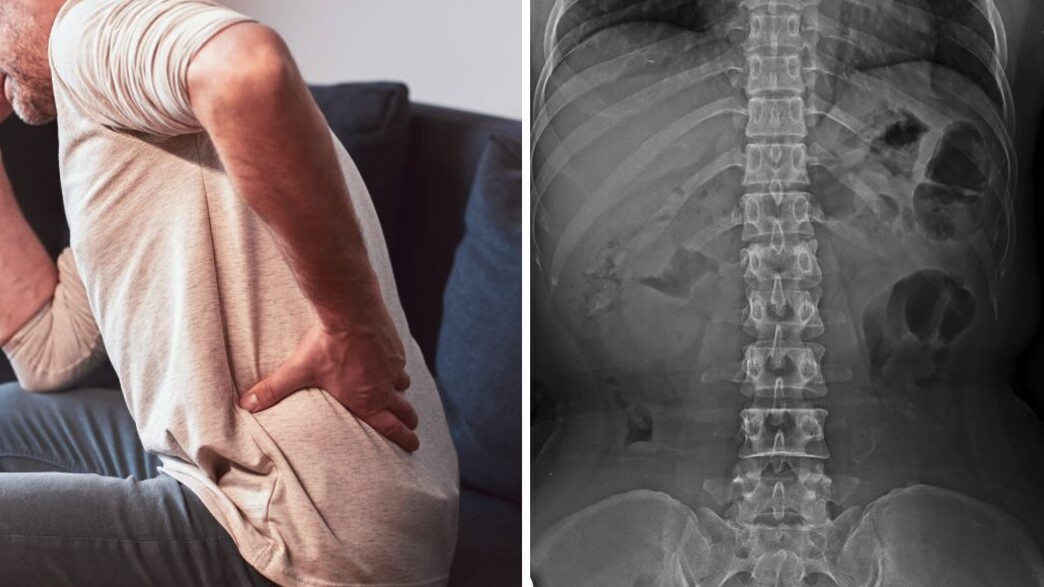

בכתב התביעה, שהגיש באחרונה עו"ד רן שפירא בשמו של הצעיר נגד קופת חולים כללית ובית החולים הדסה עין כרם, נטען כי הצוותים הרפואיים בשני המוסדות החמיצו את אבחנת 'תסמונת זנב הסוס' שממנה סבל הצעיר, והותירו אותו מוגבל לצמיתות. לדבריו, מדובר במצב חירום נוירולוגי, נדיר אך מסוכן, שבעטיו מופעל לחץ משמעותי על קבוצת העצבים המצויה בחלקו התחתון של עמוד השדרה.

עו"ד שפירא מסביר כי עצבים אלה אחראים על תחושה ותנועה ברגליים, על התפקוד המיני ועל שליטה במתן שתן וצואה, ולכן פגיעה בהם עלולה להוביל לאובדן תחושה, חולשה, הפרעות הליכה, פגיעה תפקודית משמעותית ואף לאובדן שליטה על הסוגרים.

ההיסטוריה הרפואית שלו אומנם כללה בעבר כאבי גב ואבחנה של היצרות בתעלת השדרה המותנית, אך על פי הנטען, במקום לבצע בדיקה נוירולוגית מלאה, ובמקום לשלוח את הצעיר לבדיקת הדמיה מתקדמת באופן מיידי, הוא נשלח לצילום רנטגן בלבד - בדיקה שלטענת העו"ד אינה מסוגלת לזהות פריצות דיסק או לחץ על העצבים.

לדבריו, כבר בביקור הראשון במיון היה על הצוות לבצע בדיקה נוירולוגית מלאה ולהורות על ביצוע דחוף של MRI או לפחות CT ולא להסתפק בצילום רנטגן רגיל, שלטענתו "ביצועו היה חסר תועלת של ממש, משום שהוא לא מאפשר אבחון של פריצת דיסק משמעותית או לחץ על צרור העצבים".